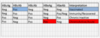

GI Portion Flashcards

(145 cards)